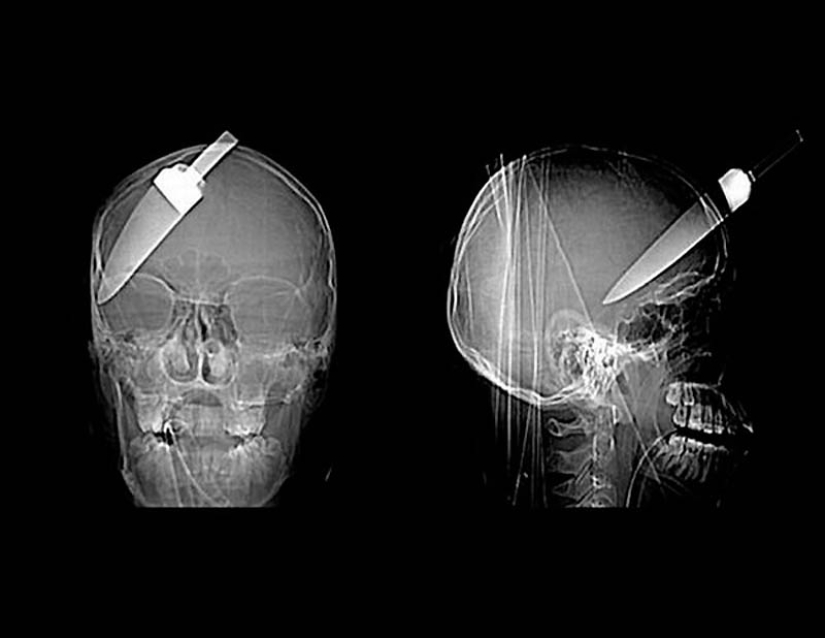

15. A knife in the head of a 10-year-old boy. The boy survived.

18. a 12-centimeter knife in the skull of a teenager.